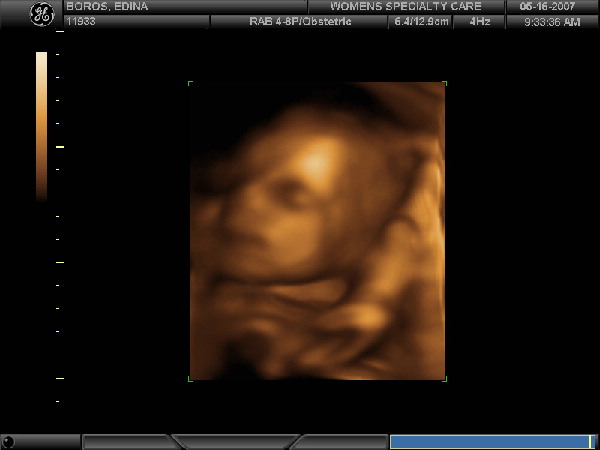

Nagyon szép a pocid, már jó méretes, az igaz, de hát azért Te már a finisben vagy.

Elhiszem, milyen jó lenne becsücsülni neked is a medencébe, de megértelek, hogy nem teszed. Tényleg elég korán itt a nagy meleg, de én most nem bánom. Azért tavaly én is nehezen bírtam nagy pocakkal. Olyan izgi, hogy már csak pár hét és Te is megint babázol!